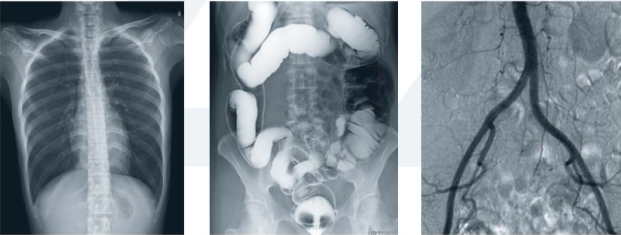

近年來隨著醫(yī)學影像技術的普遍成熟,平板式DR成像系統(tǒng)已經成為醫(yī)院及放射科醫(yī)生在選擇醫(yī)療設備時關注的重點。平板式DR成像系統(tǒng)所獲圖像質量高、工作效率快、圖像后處理技術操作方便,可為醫(yī)院帶來更大的經濟效益。

隨著數(shù)字化攝影的不斷發(fā)展,平板式DR成像系統(tǒng)的功能優(yōu)勢將越來越為醫(yī)院所認識,比如:

一、透視功能

常規(guī)DR在診斷成像方面有局限性。在某些特殊位置,只有一張平底膠片會導致診斷失敗或誤診。例如,某些結節(jié),內側潛在肋骨骨折等的診斷成像應使用熒光檢查通過DR進行。平板式DR成像系統(tǒng)動態(tài)照相檢查,在視覺條件下準確確認病變位置可以充分避免這些問題。

平板式DR成像系統(tǒng)透視影像

二、高清點片(900萬像素)功能

高清點片又稱高清動態(tài)點片,在平板式DR成像系統(tǒng)動態(tài)拍攝如透視的條件下,對病變部位進行可視化觀察,待發(fā)現(xiàn)疑似病變部位的時候進行瞬間點片,從而能夠準確獲取病變部位的高清影像用于臨床診斷,從而大程度上降低漏診誤診率。

三、透視+高清點片功能,缺一不可

透視過程是為了發(fā)現(xiàn)疑似病灶。但機器如果不能同時進行毫秒級高清點片,那就不能實現(xiàn)透視過程中高清圖像的所見即所得。正是因為有了毫秒級高清點片(900萬像素)功能,平板式DR成像系統(tǒng)才能夠在發(fā)現(xiàn)疑似病灶的情況下迅速獲取高清靜態(tài)圖片,方便醫(yī)生對病情的進一步診斷。毫秒級高清點片功能非常大地提高了DR的準確診斷能力。